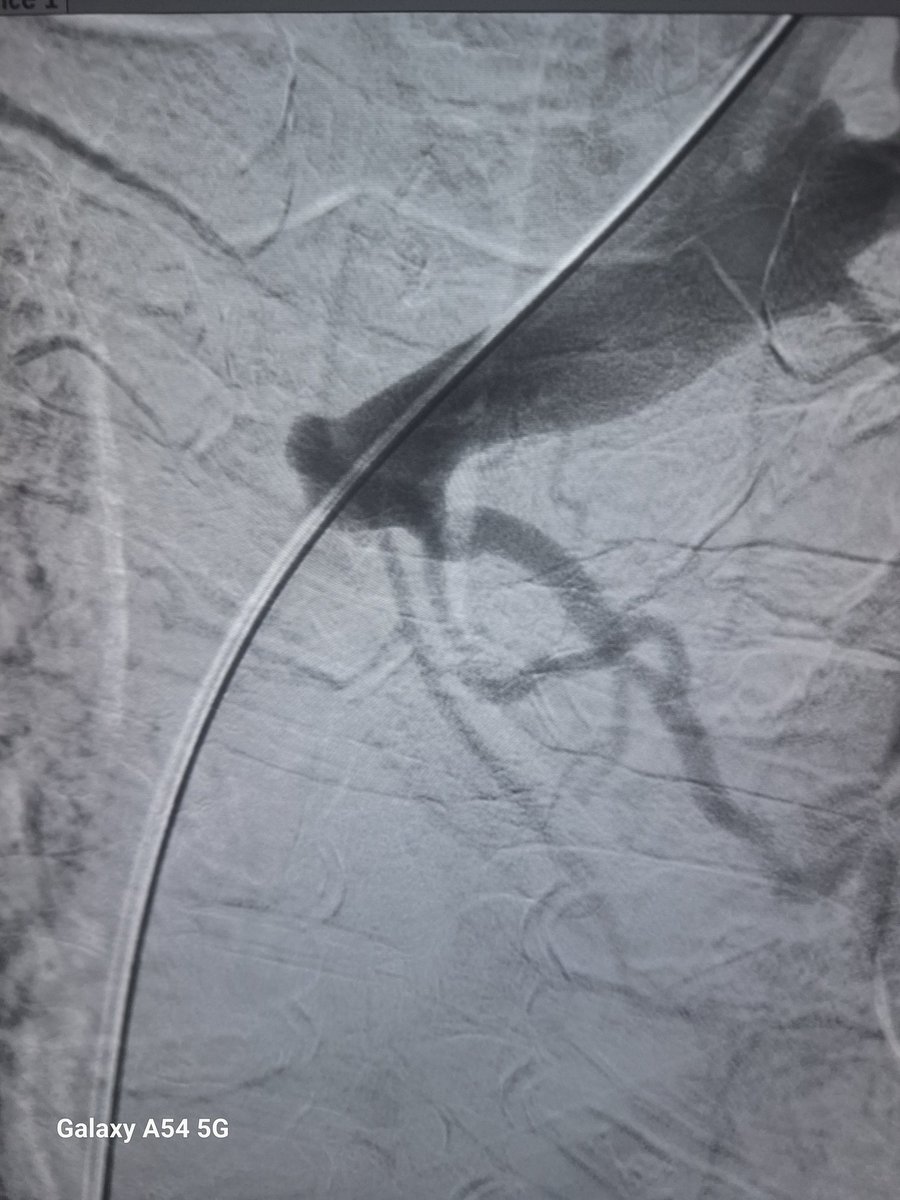

Friday used to be access day during training @sctimst_tvm , @PShivanesandr guiding us through AVF's daylong. Todays case @tenderpalm_lko, Patient diagnosed JXA stenosis n came from far to get his AVF serviced as he was feeling a pulse . @VarenyamVasc #accessed @theveincon

vascularsrgn's tweet image. Friday used to be access day during training  @sctimst_tvm , @PShivanesandr  guiding  us through AVF's daylong. Todays case  @tenderpalm_lko, Patient diagnosed JXA stenosis n came from  far to get his AVF serviced as he was feeling a pulse . @VarenyamVasc #accessed @theveincon